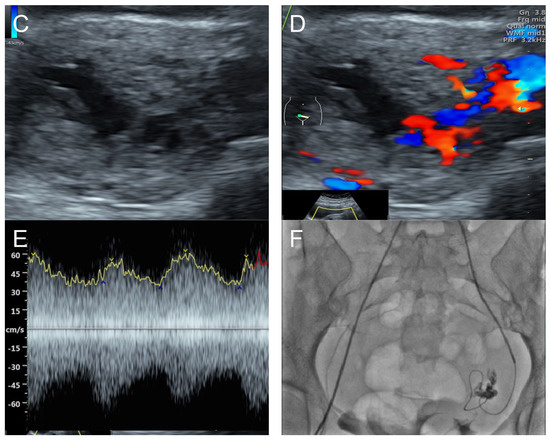

(A–C) Transabdominal grayscale ultrasound: cross-sectional, sagittal, and oblique scans of the uterus showed heterogeneous soft tissue content, like pieces of conceptive product in the uterine cavity; ill-defined endometrial–myometrial interface; hypoechoic lacunae varying in size in the non-specific tissue content, mainly localized at the left anterior wall. (D) Color flow mapping with a relatively high pulse repetition frequency of 3.2 kHz (applied to the same image (C)) showed hyper-vascularized lesions in the myometrium; multidirectional flow, mainly localized at the left anterior wall; and some cystic spaces of no flow, indicating lysed blood in the cavity. (E) Spectral Doppler ultrasound showed a high peak systolic velocity (approximately 60 cm/s). The sonographic diagnosis was uterine AVM. The main differential diagnoses were incomplete abortion (conceptive products) and gestational trophoblastic disease. (F) CTA during uterine embolization revealed hypervascularity and tortuous arterial anatomy enhancing a dilated vascular pouch overlying the endometrium of the uterus with feeding via the bilateral uterine arteries and draining via the internal iliac veins, confirming uterine AVM; low blood content in the uterine cavity without evidence of active contrast extravasation.

Management: Initial therapy included blood transfusion, tranexamic acid administration, and intrauterine tamponade with a Foley catheter balloon, resulting in less but continued bleeding. Emergency uterine artery embolization on both sides, using glue (Glubran 2 cyanoacrylate) mixed with Lipiodol (iodized oil), was successfully performed. The follow-up abdominal CTA at 8 weeks after the procedure showed no residual AVM, and the patient was healthy with no longer abnormal bleeding at 3-year follow-up.